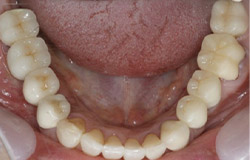

インプラントで噛み合わせの再構成を伴った症例。

治療後のメンテナンスを行わないと

周囲炎になるリスクあり。